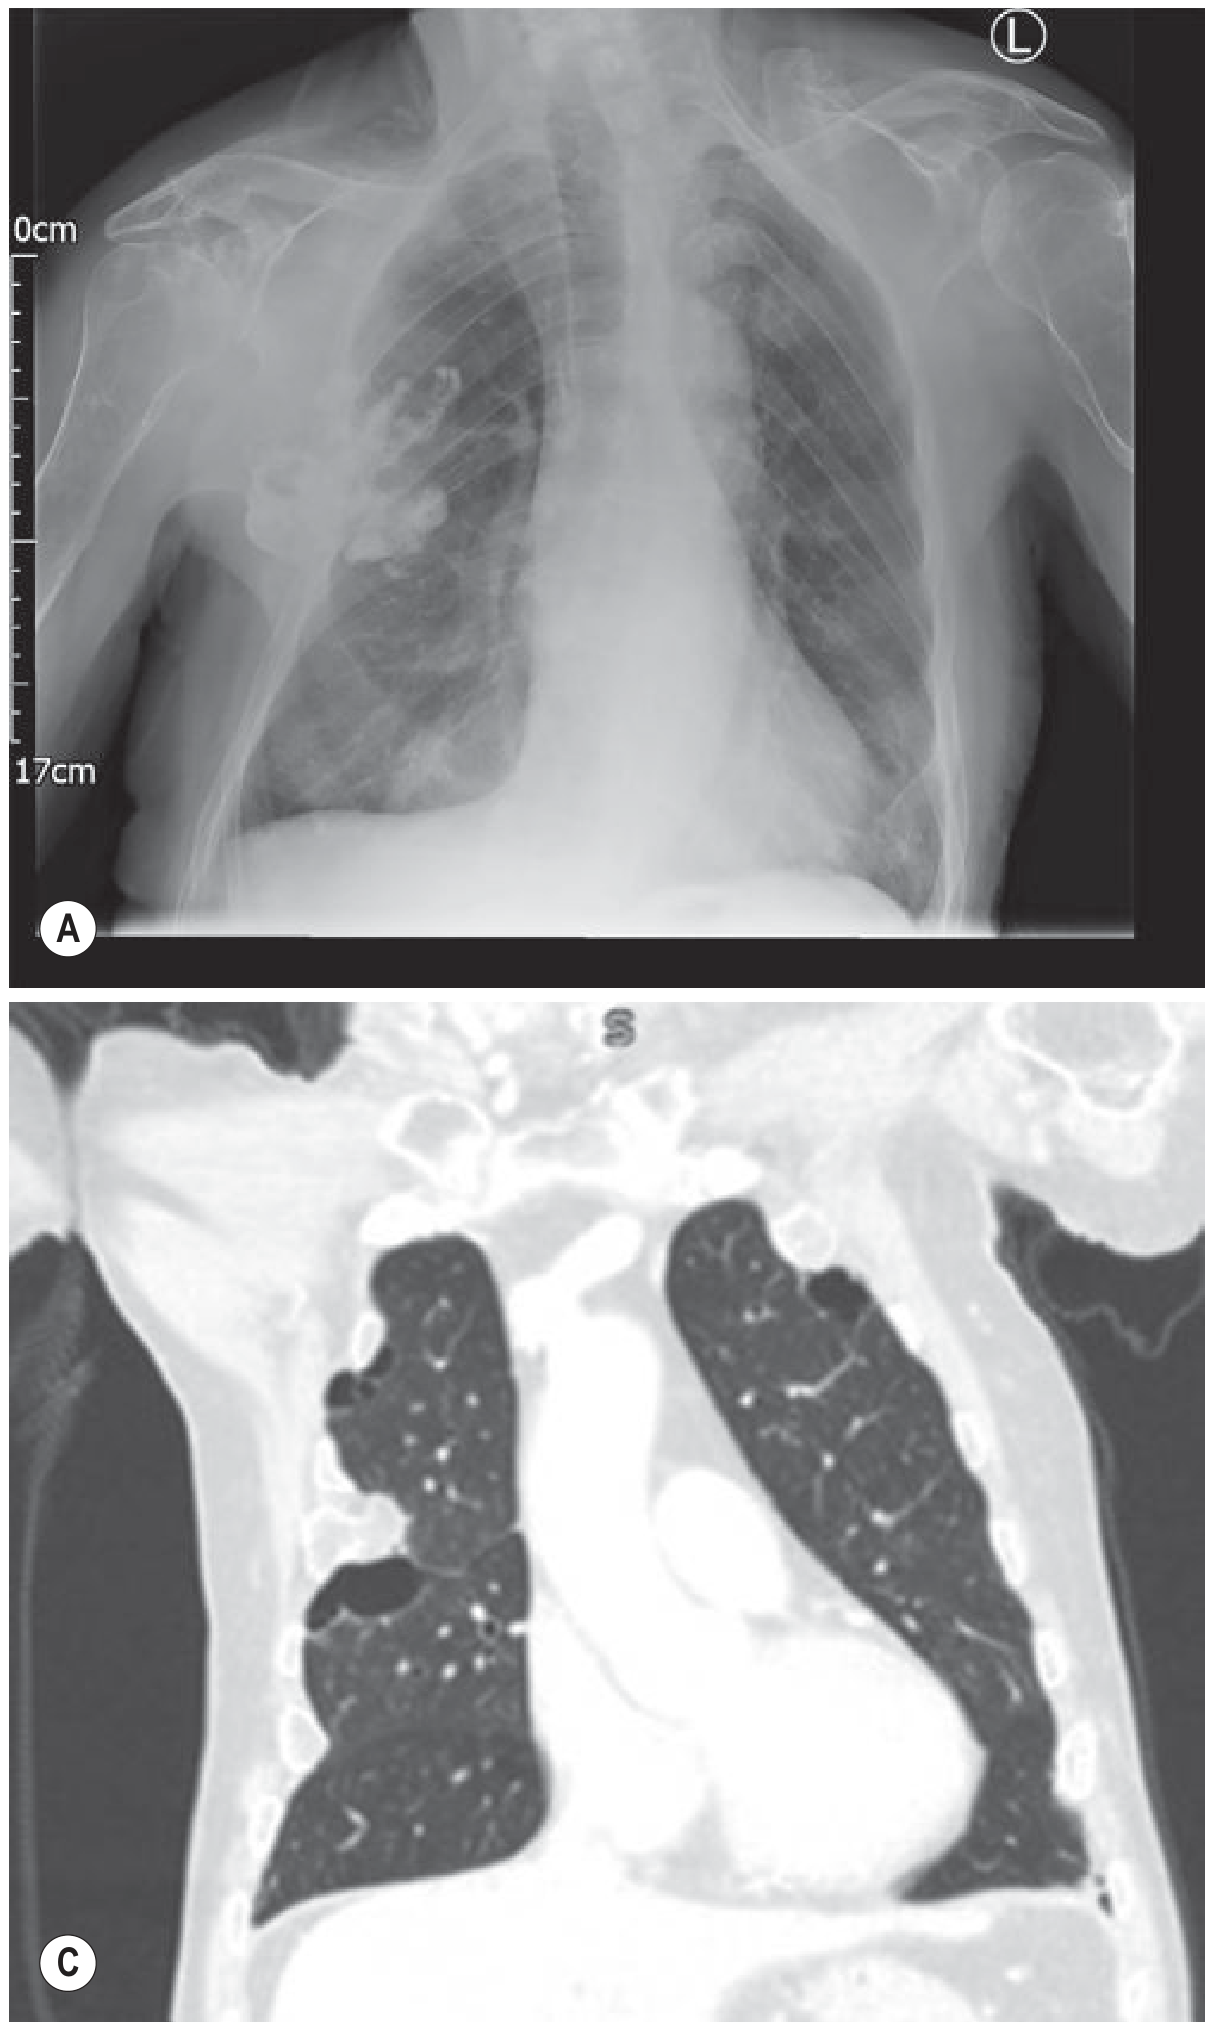

PA chest radiograph and CT showing bilateral pleural effusions — note layering fluid on the left with the meniscus sign

CXR (A) and CT (C) demonstrating pleural effusion with the meniscus sign and dependent layering — Grainger & Allison's Diagnostic Radiology

• Small effusion (<200–500 mL): initially subpulmonary/invisible; first sign is blunting of the posterior then lateral costophrenic angle

• Moderate effusion: homogeneous opacity with obliteration of the costophrenic angle and hemidiaphragm; meniscus sign (concave upper border, higher laterally)

• ~1000 mL: reaches the level of the 4th anterior rib

• Massive effusion: dense opacification with contralateral mediastinal shift

• Lateral decubitus view: fluid layers and the lung floats — increases sensitivity for small effusions